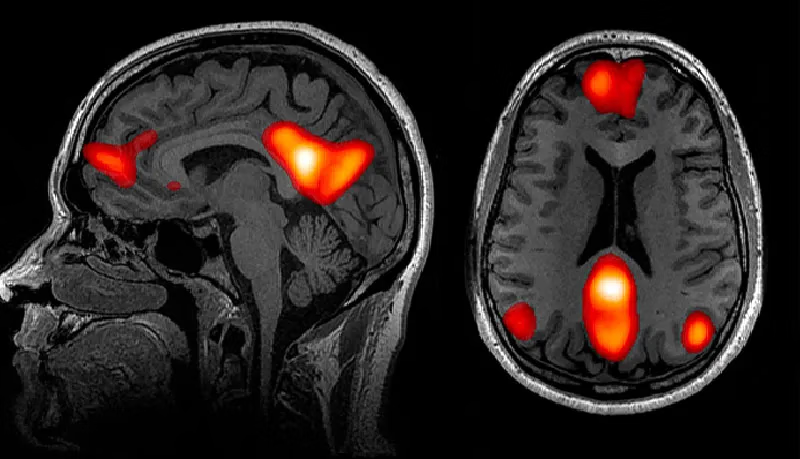

有趣的是,他们于2020年发表在《自然通讯》杂志上的研究结果显示[12],与孤独感对应的大脑区域是默认网络(default network)。他们发现,在孤独人群中,默认网络不仅体积更大,而且与大脑其他部位的连接也更加紧密。

直到20多年前,科学家们才知道有默认网络的存在。它是一个耗能大,且当个体处于精神漫游状态时会被激活的大脑区域。此外,之前的研究显示,默认网络似乎与人类进化过程中形成的许多独特能力有关,如语言、预测未来和因果推理等能力。比如,在日常生活中,当我们想起他人时,或试图揣测他人意图时,默认网络就会被激活。

上述研究的结果与心理学家之前的发现不谋而合,即处于孤独状态的人往往会在脑海中幻想社交互动,容易念旧,甚至会将宠物拟人化,例如,把猫当人类一样进行交谈。布兹多克(Bzdok)表示:“这些行为都需要默认网络的参与。”

诚然,孤独可以在想象中带来丰富的“社交生活”,但同时也削弱了人们对真实的面对面社交接触的欲望。2021年,布兹多克及其同事的一项研究也揭示了这一点[13]。他们分别观察了处于社交孤立状态下的人和缺少社交支持(衡量标准是日常生活中是否有倾诉对象)的人的功能脑成像数据。结果发现,在所有这些人中,与奖赏相关的眶额叶皮质的体积都较小。这可能意味着,孤独感让大脑不易从社交中获得奖赏,进而觉得想象中的社交和现实中的社交并无区分。

最近的一些脑成像研究也支持这一观点,即孤独感深植于我们的内心。在一项研究中[16],剑桥大学神经科学研究助理利维娅·托莫娃(Livia Tomova)和同事们扫描了40位被试者在禁食10小时后观察美食图片时的大脑活动。同样地,他们让这群人独处10个小时——期间不能使用电话、电子邮件等可以与他人联结的媒介,甚至不能阅读小说。随后,他们让被试者看朋友们的照片。有趣的是,科学家们比较这两组实验结果发现,在饥饿和孤独时,人们的大脑激活模式非常相似。